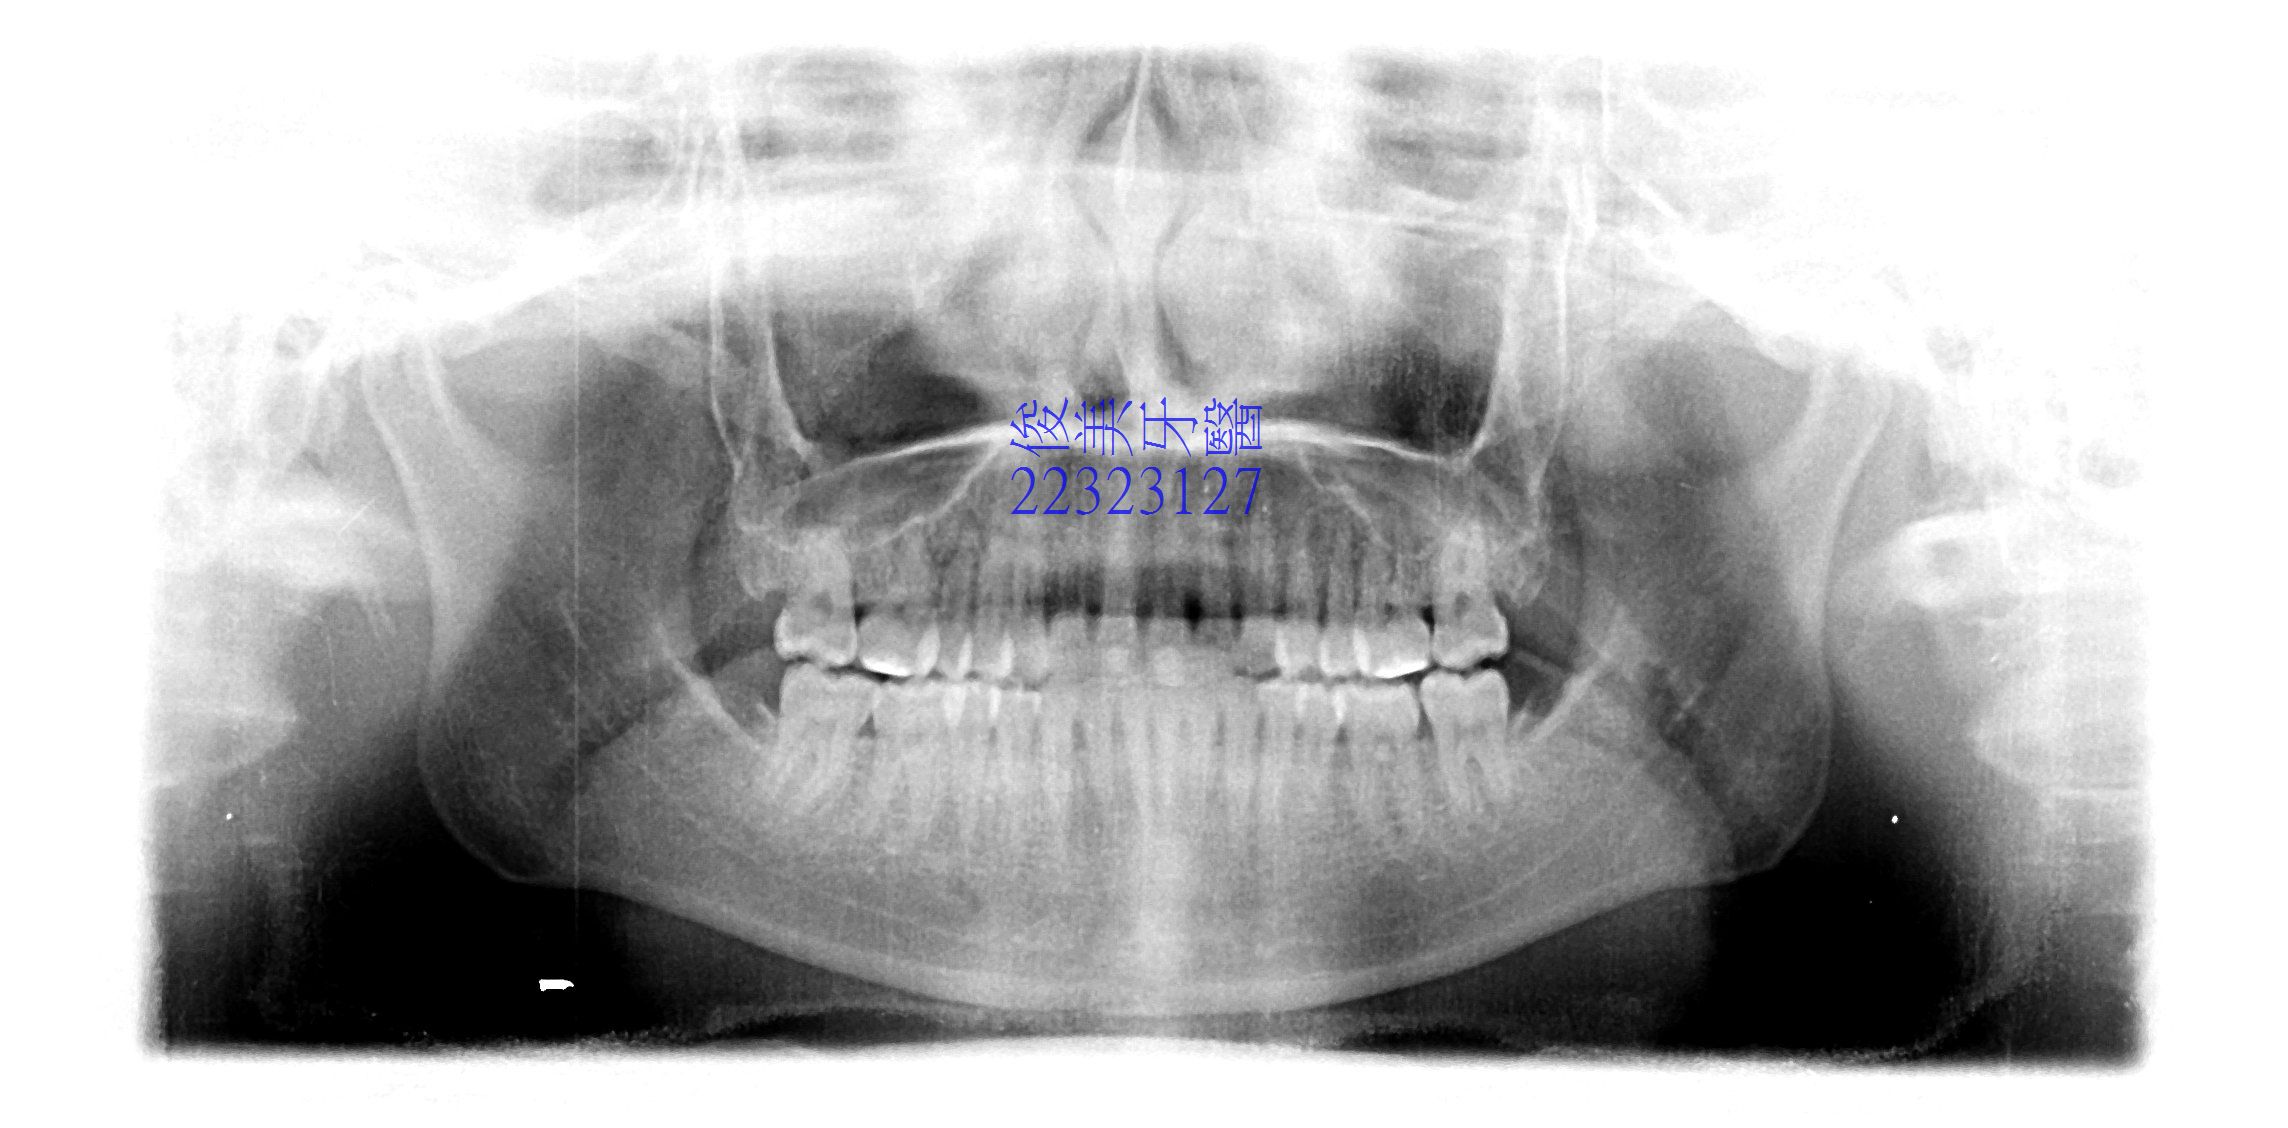

![]() 患者於門診中表示,牙齒很擁擠,想要改善;經醫師門診後,建議患者進行矯正治療即可改善。 ![]() 牙齒重疊... ![]() 有深咬現象... ![]() 上顎狀況... ![]() 下顎狀況... ![]() 左側咬合,牙齒往舌側傾斜...... . ![]() 右側咬合,牙齒往舌側傾斜...... ![]() 治療中....擁擠和深咬已改善.... ![]() 牙齒往後移.....將牙齒齒軸回正一點。 ![]() 治療結束,拆除矯正器了............. ![]() 患者好開心......牙齒整齊後,笑容更可愛了。 ![]() 也沒有暴牙的狀況。 ![]() 上顎牙弓狀況。 ![]() 下顎牙弓狀況。 ![]() 右側咬合狀況。 ![]() 左側咬合狀況。 ![]() 已拆除超過5年,依舊配戴維持器,保持最佳狀態。 |